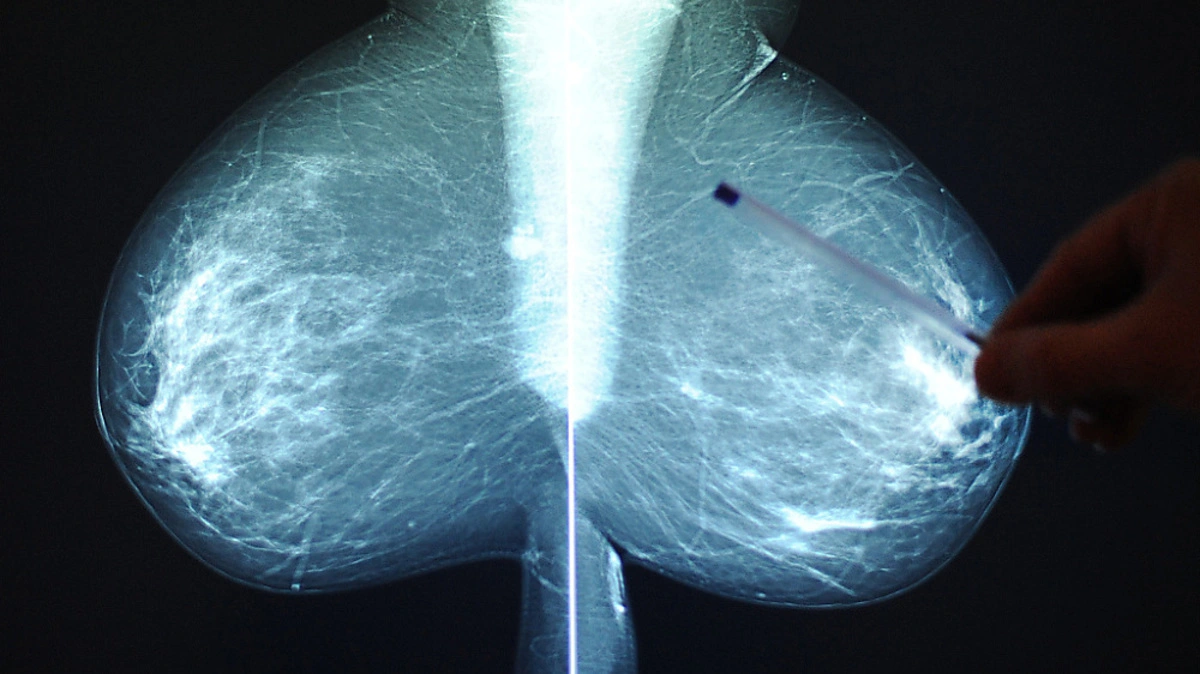

Das Röntgenbild gehörte zu einer anderen Patientin mit (fast) identem Namen (Symbolbild)

© APA/THEMENBILD